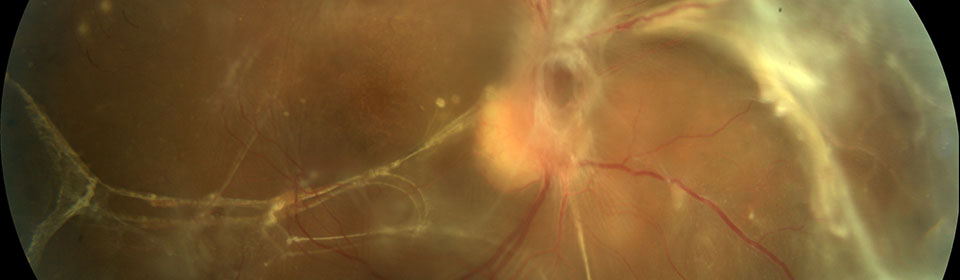

Almost 1 in 10 diabetics has sight threatening retinopathy.

Diabetes is the leading cause of blindness in the 25 to 75 age group.

There are no early symptoms.